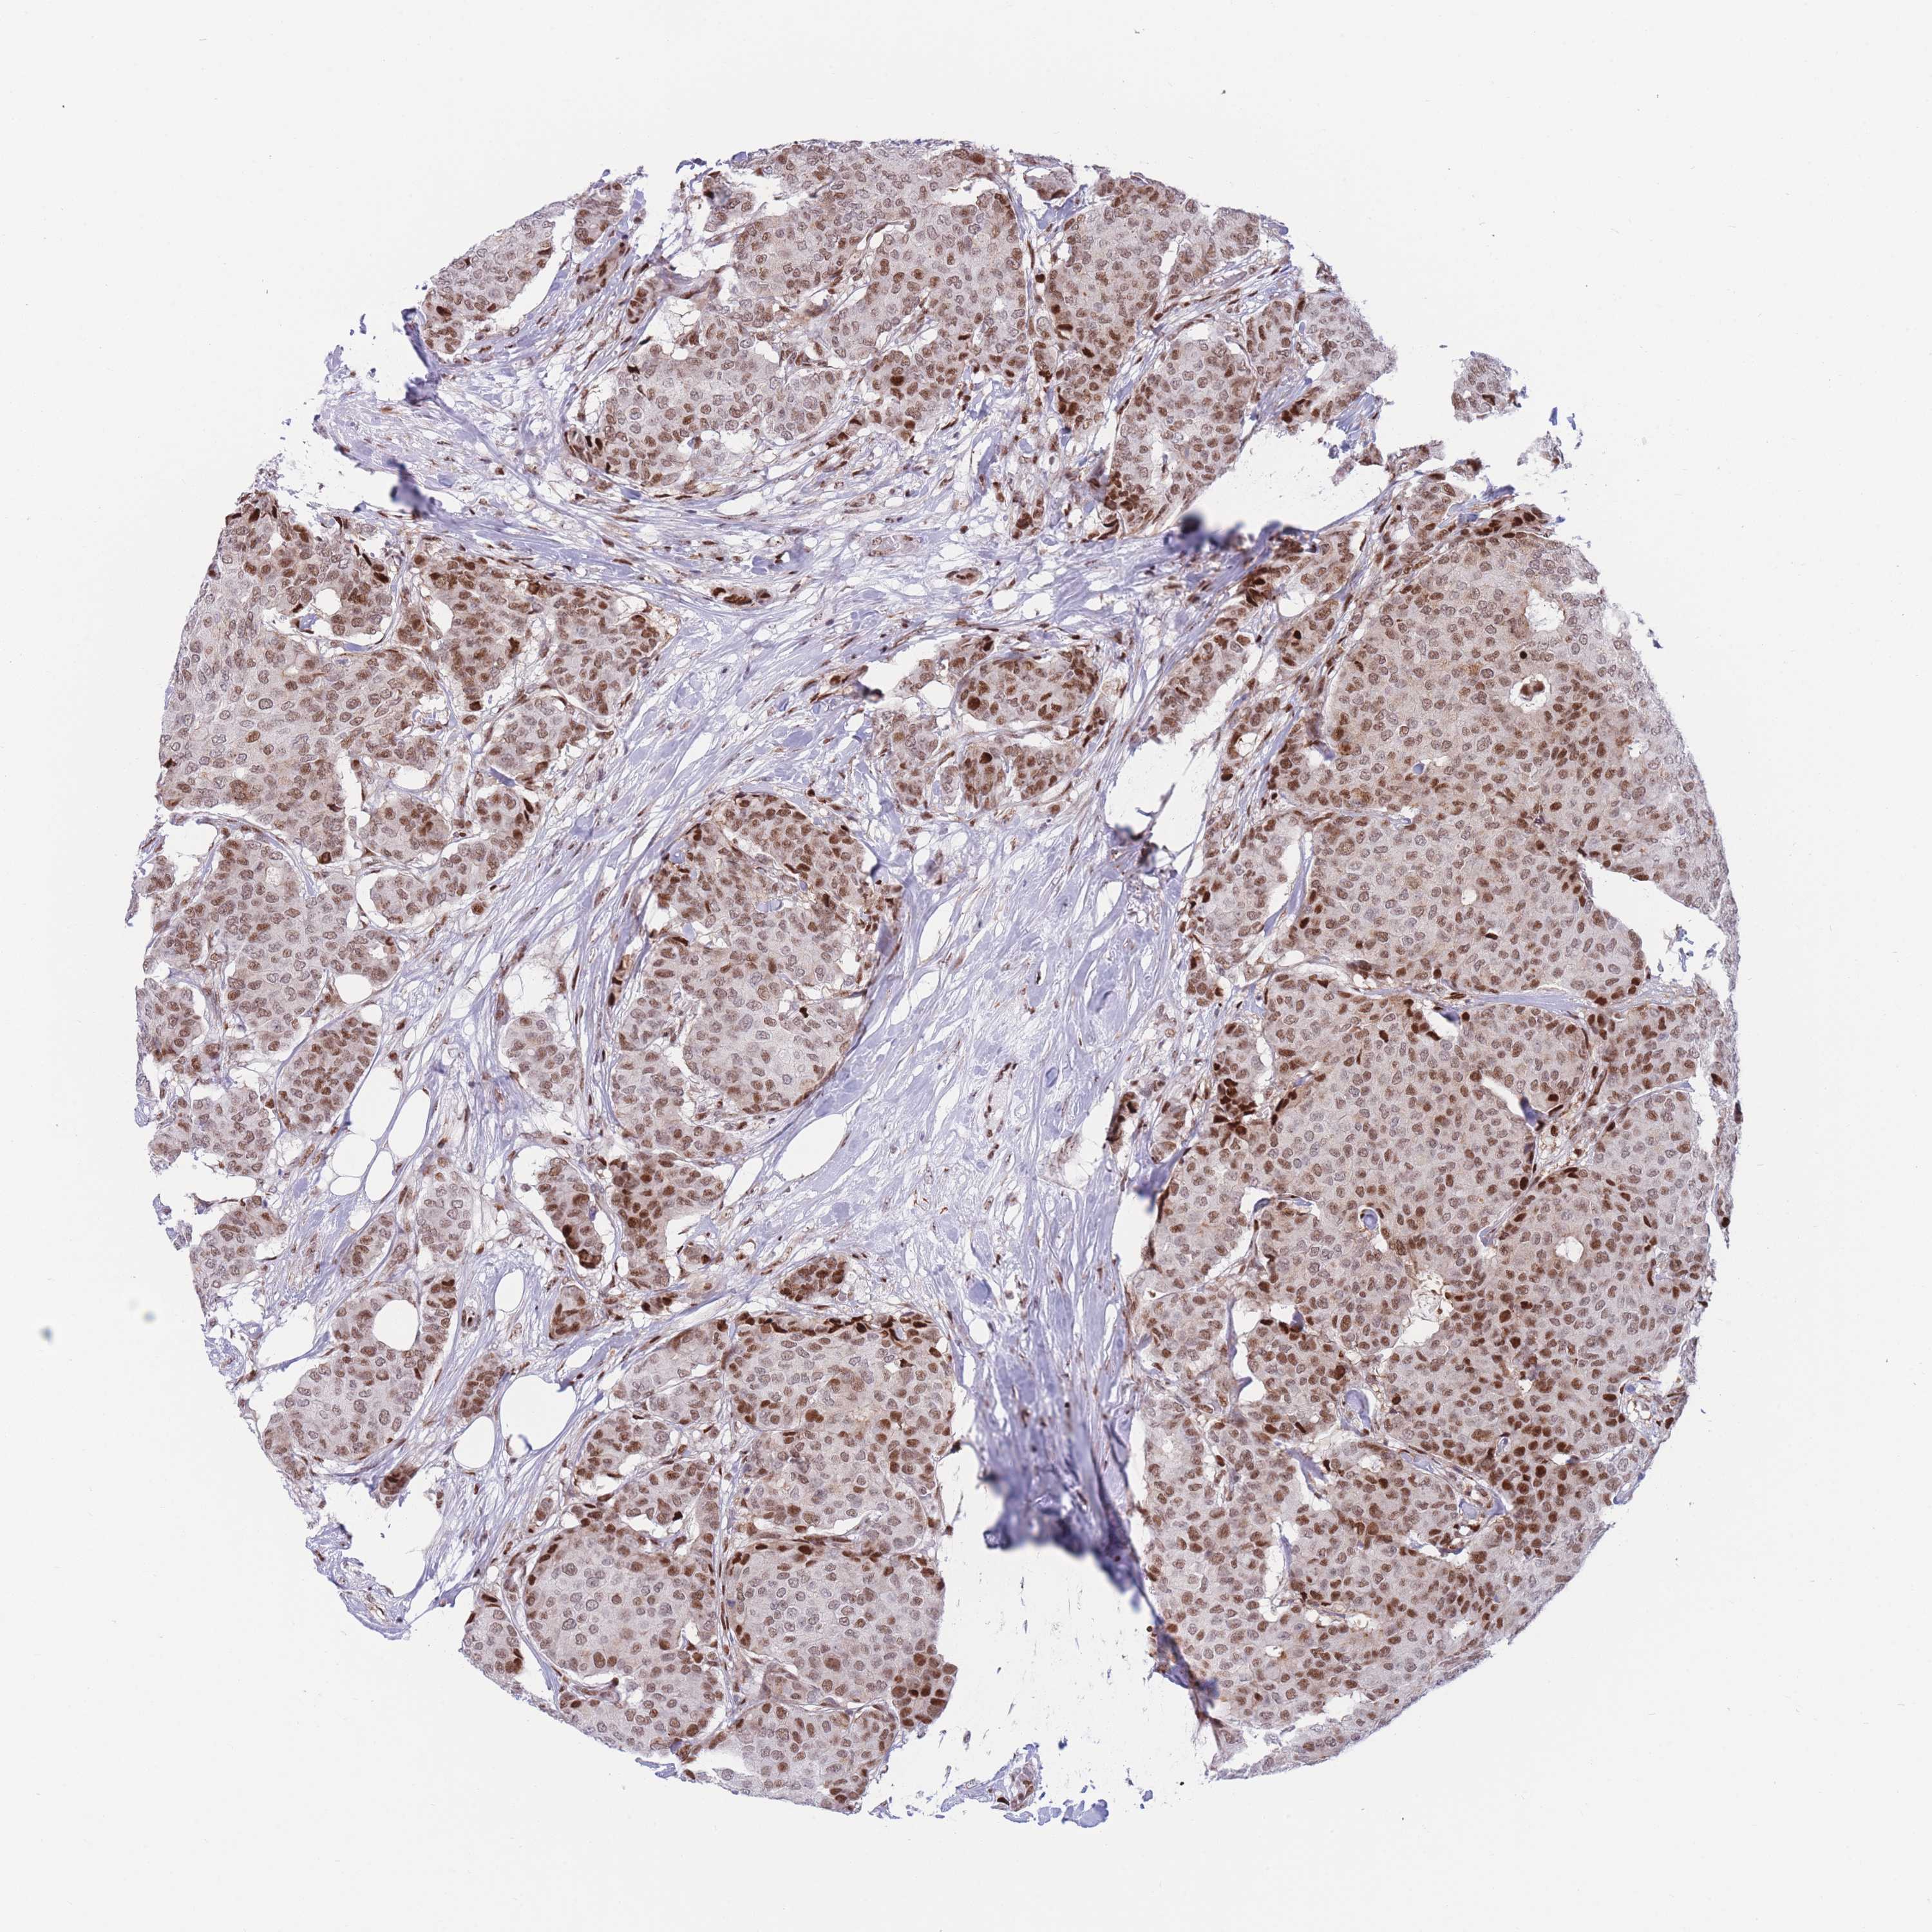

CANCER BREAST CANCER Show tissue menu

BRCA TCGA BRCA VALIDATION PROTEIN EXPRESSION